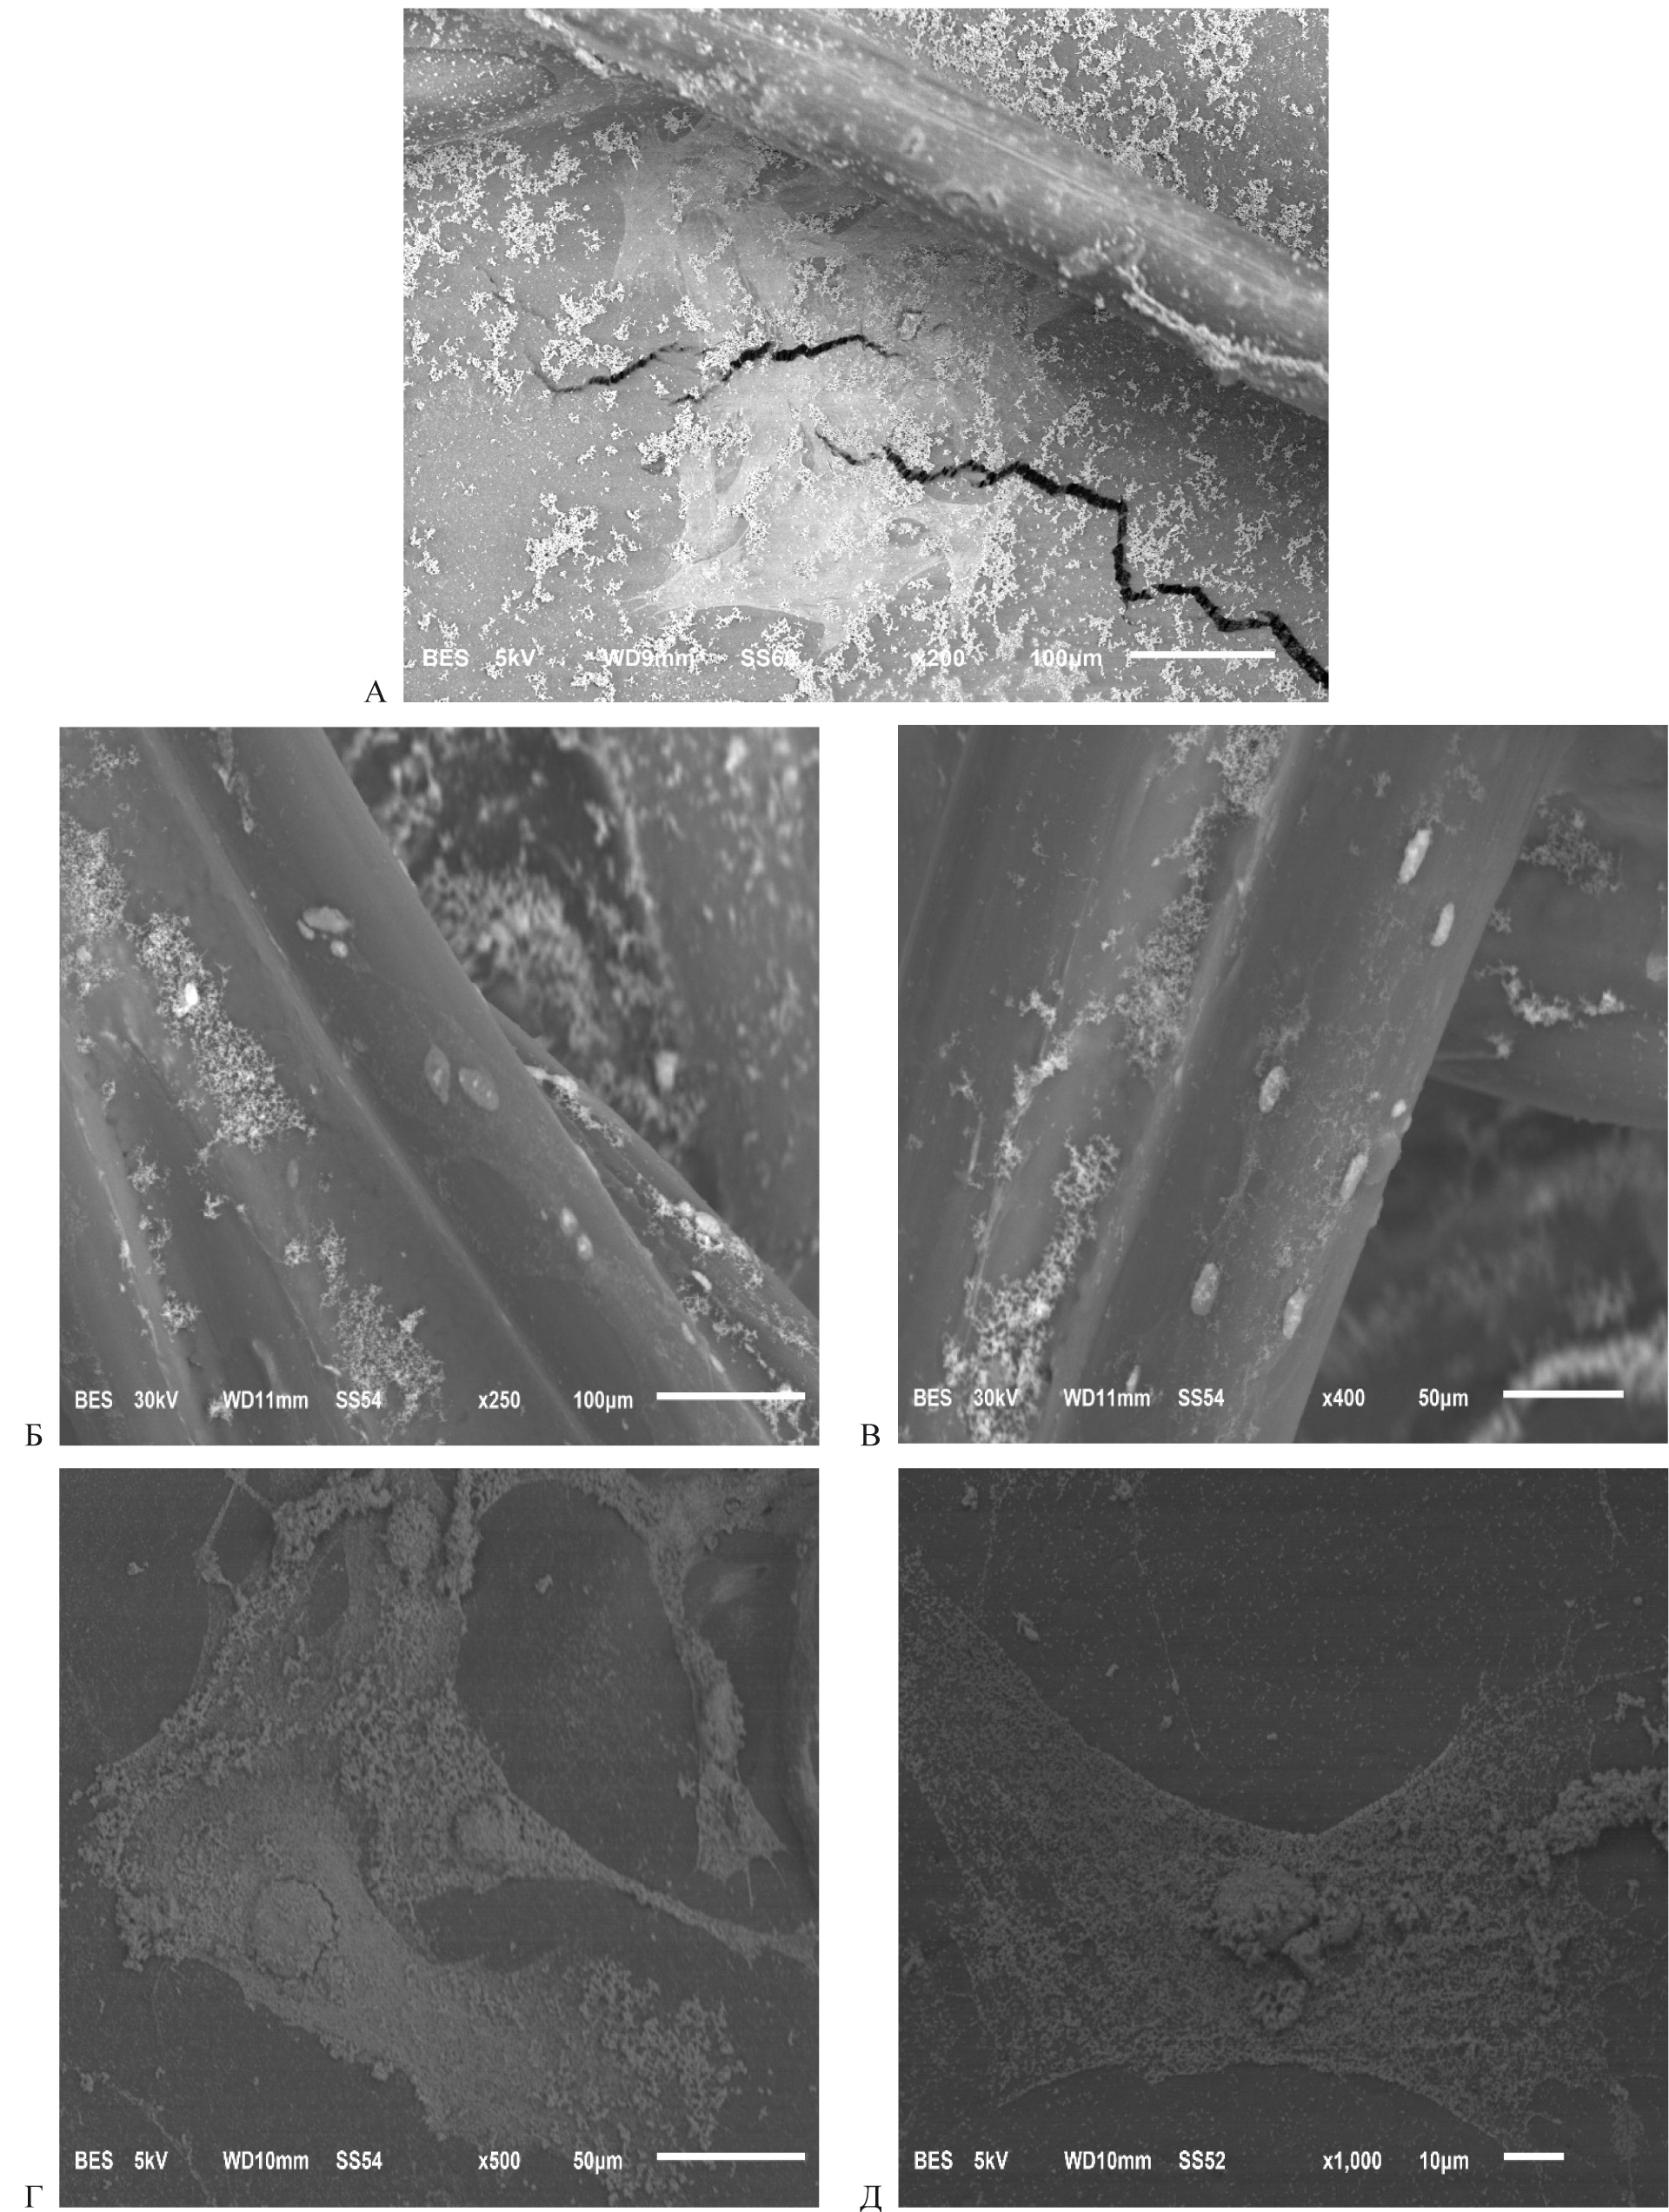

В результате полученных исследований было выявлено, что после культивирования дермальных аутофибробластов в течение 5 суток происходит их прикрепление к нитям эндопротеза. В группе с использованием герниопротеза «Унифлекс стандартный» на нитях синтетического материала визуализировались единичные клетки округлой или овальной формы. Большая часть клеток прикреплялась ко дну флакона, приобретая характерную распластанную форму с большим количеством отростков (рис. А).

В группе «Унифлекс стандартный» с последующей обработкой поликапролактоном вокруг нитей протеза визуализировались группы фибробластов. Большая часть клеток имели распластанную или вытянутую форму, что свидетельствует о прочности прикрепления к материалу (рис. Б, Д). Важно, что клеточный рост определялся как вокруг мест переплетения, так и между прямыми нитями.

Рис. Микрофотография при электронной микроскопии поверхности сетчатого эндопротеза «Унифлекс стандартный». СЭМ: А – без предварительной обработки протеза (ув. ×200 × 10-6); Б – с обработкой поликапролактоном (ув. ×250 × 10-6); В – с обработкой поликапролактон + низкотемпературная плазма (ув. ×400 × 10-6); Г – с обработкой поликапролактоном (ув. ×500 × 10-6; Д – с обработкой поликапролактон + низкотемпературная плазма (ув. ×400 × 10-6)

В группе «Унифлекс стандартный» с обработкой поликапролактон + низкотемпературная плазма также определялось прикрепление фибробластов к герниопротезу. При этом клетки преимущественно располагались поодиночке, имели округлую форму и локализовались только на прямых нитях, а в местах плетения отсутствовали (рис. В, Г). С учетом достаточно упорядоченного клеточного «рисунка» можно предположить, что клетки плотно фиксировались в местах насечек, полученных в результате обработки низкотемпературной плазмой. Такой способ обработки синтетического материала подходит для исключительно стерильных условий, так как данные насечки могут служить местом локализации не только клеток соединительной ткани, но и бактерий.